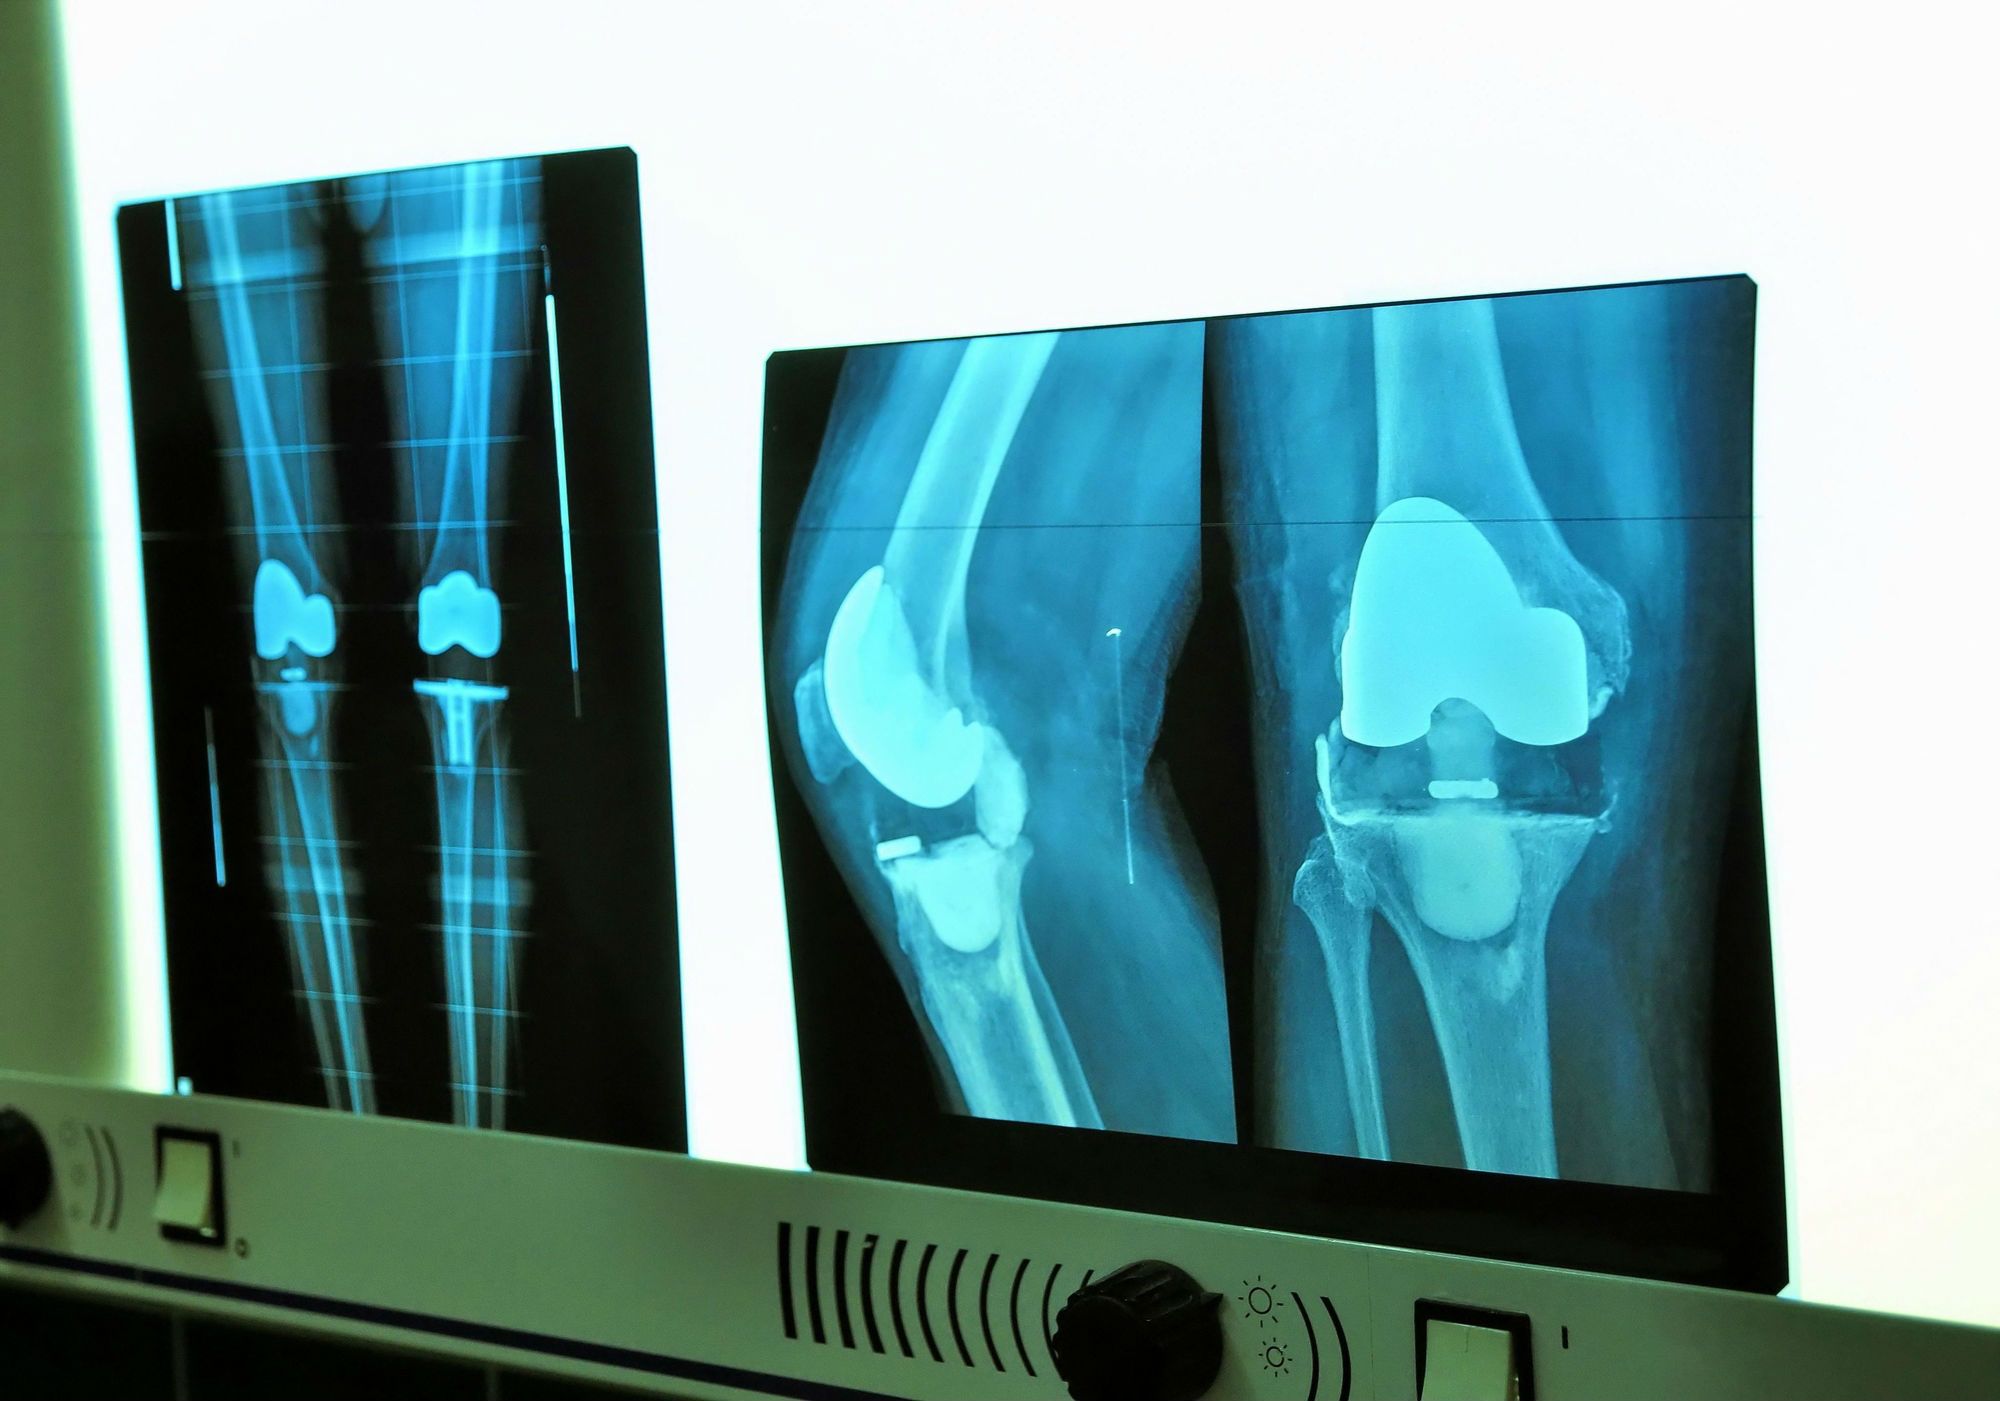

Problems With Zimmer Knee Replacements . Specialist lawyers at irwin mitchell have been contacted by worried patients who underwent knee replacement surgery with two. Unfortunately, some of the components used in zimmer knee replacements have suffered unanticipated high failure rates. Indications of loosening include radiolucent lines on imaging tests, which are large gaps between the device and bone. If you experience any pain or other problems associated with nexgen knee implants (for example a limp, inability to bear weight,. Problems associated with this implant can cause serious complications and patients can face the risk of loosening of their tibial component. A recalled knee replacement system has kicked off new product liability litigation in georgia after a recipient alleged portions of the. The largest knee implant maker in the world recently recalled thousands of its persona knee implants, leading the food and drug administration to issue a warning that the implants can loosen early and cause complications. While problems can occur, knee replacement, also called knee arthroplasty, typically has high success rates. The manufacturer, zimmer, says its recall is voluntary.

Specialist lawyers at irwin mitchell have been contacted by worried patients who underwent knee replacement surgery with two. A recalled knee replacement system has kicked off new product liability litigation in georgia after a recipient alleged portions of the. The manufacturer, zimmer, says its recall is voluntary. If you experience any pain or other problems associated with nexgen knee implants (for example a limp, inability to bear weight,. Unfortunately, some of the components used in zimmer knee replacements have suffered unanticipated high failure rates. The largest knee implant maker in the world recently recalled thousands of its persona knee implants, leading the food and drug administration to issue a warning that the implants can loosen early and cause complications. Problems associated with this implant can cause serious complications and patients can face the risk of loosening of their tibial component. Indications of loosening include radiolucent lines on imaging tests, which are large gaps between the device and bone. While problems can occur, knee replacement, also called knee arthroplasty, typically has high success rates.